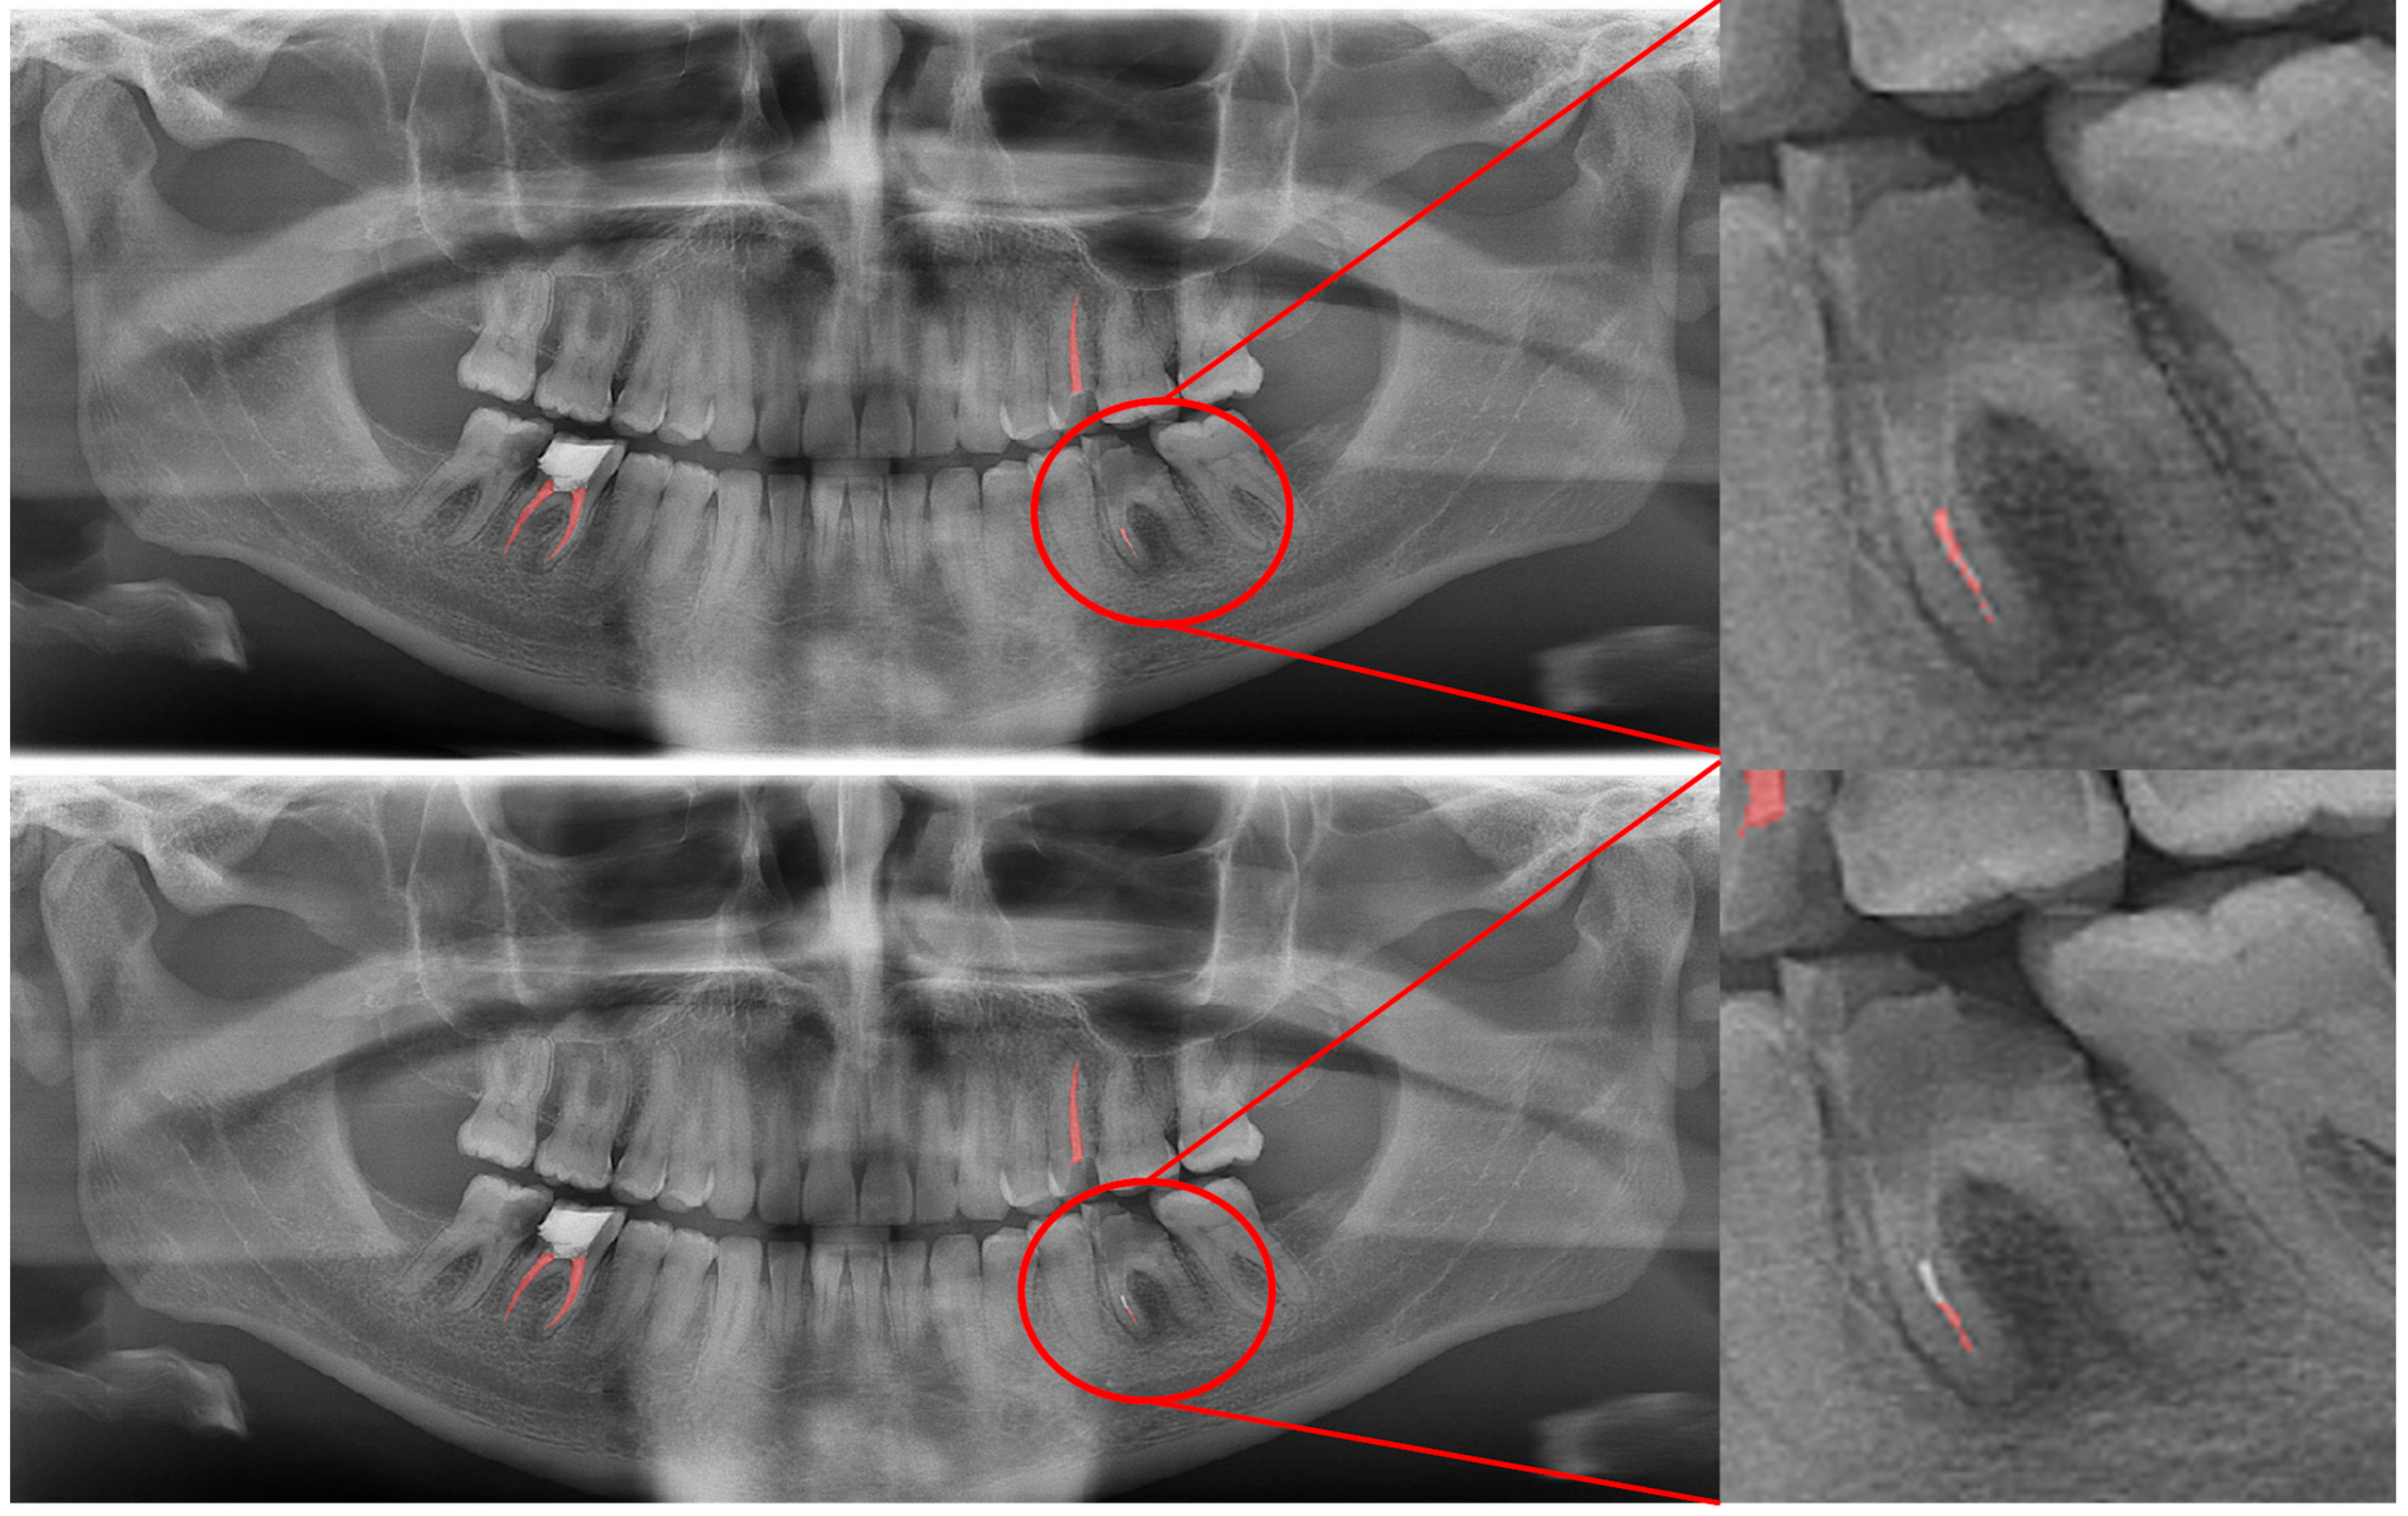

Figure 10.

A wide amalgam restoration in the mandibular left first premolar tooth was mis-segmented as a crown restoration. Manual segmentation (upper image) and automatic segmentation (lower image) can be seen above.

In Figure 8, a more successful automatic segmentation is observed at the maxillary right third molar than the maxillary left third molar, and a missing segmented area in the form of a notch is observed. As most of the upper third molars were superimposed on the floor of the maxillary sinus and zygomatic process of the maxilla, erroneous segmentations were inevitable. In Figure 9, an erroneous automatic segmentation at the mandibular left second molar due to the superimposition between the mandibular left first and mandibular left second premolars can be seen.

In Figure 10, it can be seen that a wide amalgam restoration in the mandibular left first premolar tooth was mis-segmented as a crown restoration. The mis-segmentation of wide amalgam restorations was seen in a total of five OPGs.

In Figure 12, an erroneous segmentation of an unsuccessful root canal filling can be seen. While our model had a fair DSC value for successful root canal treatments, it was seen that cases with inadequate root canal fillings and gutta-perchas that superimposed with the neighboring teeths’ roots caused a relatively lower DSC value.